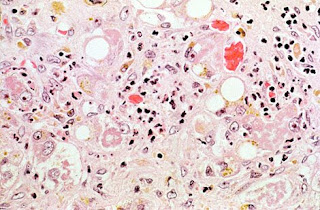

Lâmina 62 (Doença de Gaucher)

Imagem escaneada da lâmina de baço na doença de Gaucher. Notar a área proporcionalmente grande de polpa vermelha, que tem cor rósea.

POLPA VERMELHA: contém macrófagos de citoplasma róseo muito volumoso, que armazenam cerebrósides, um tipo de esfingolípide. A doença de Gaucher é uma esfingolipidose, condicionada por um gene autossômico recessivo. O tipo mais comum ocorre em adultos e leva a grande hepatoesplenomegalia, por acúmulo de esfingolípides em macrófagos por falta da enzima glicocerebrosidase. Por causa do acúmulo, os macrófagos ficam parecendo células epiteliais, e o volume da polpa vermelha fica muito maior que o normal, sobrepujando grandemente a polpa branca.